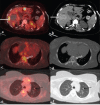

Primary cardiac tumors are rare with angiosarcoma being the most common among malignant cardiac tumor. We present a case of 30-year-old female patient in whom F-18-fluorodeoxyglucose positron emission tomography/computed tomography demonstrated a necrotic mass in right atrium with multiple fluorodeoxyglucose avid lesions in both upper and lower alveolus, liver, multiple bones, and bilateral lungs. Patient underwent biopsy from gum swelling which revealed metastatic angiosarcoma.